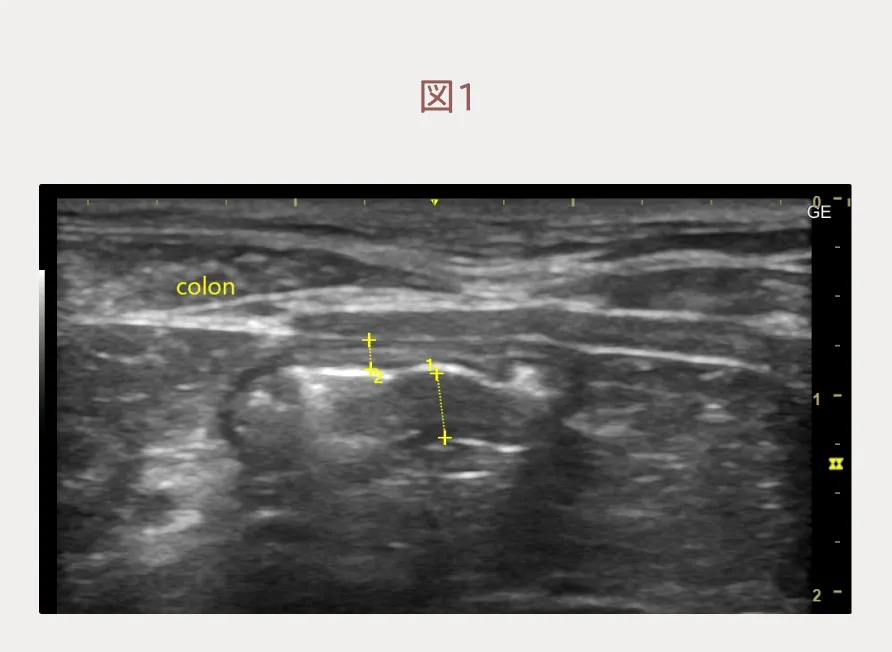

身体検査では軽度のやせ型で、皮膚のフケ(落屑)がみられました。食事量を変えていないのに健常時から11%の体重減少を認め(60kgの成人が6.6kg痩せるのと同じです。)、身体検査で栄養不良が随所で感じられました。血液検査ではアルブミンは基準範囲の下限値(2.3 g/dl)でした。エコー検査では大腸壁の一部は層構造が不明瞭で壁肥厚を認めました。(図1)